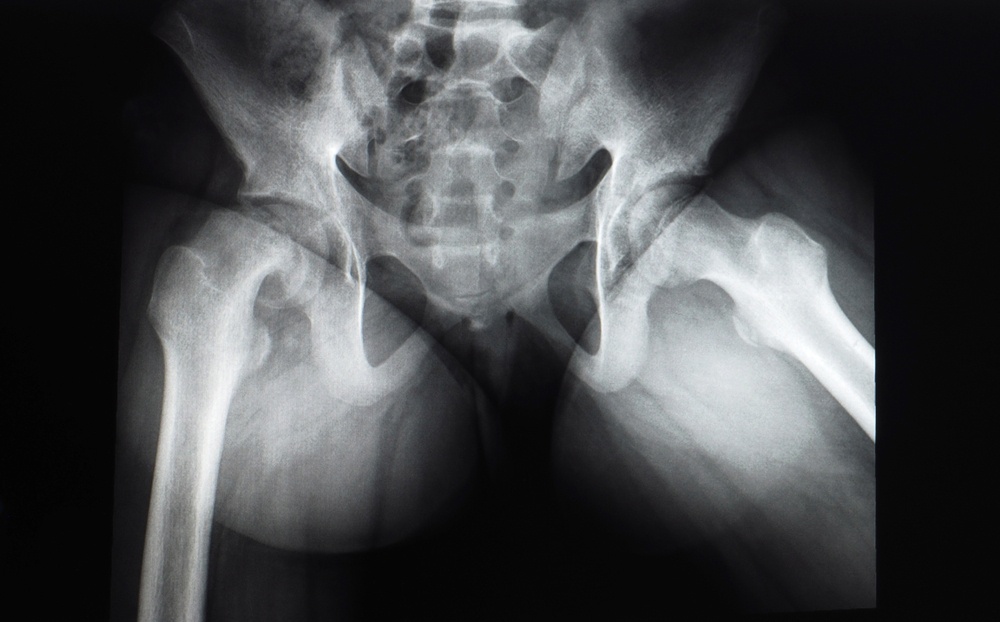

In medicina, con il termine sublussazione si intende la perdita parziale dei normali rapporti tra i capi articolari. La sublussazione è considerata il grado più lieve della lussazione, che invece consiste nella perdita totale e permanente dei normali rapporti fra i due capi ossei che costituiscono un’articolazione.

- In caso di sublussazione dell’anca, la testa del femore del bambino risulta più o meno spostata rispetto alla cavità acetabolare dove risiede normalmente.

- In caso di lussazione dell’anca invece, la testa del femore fuoriesce completamente dalla cavità acetabolare.